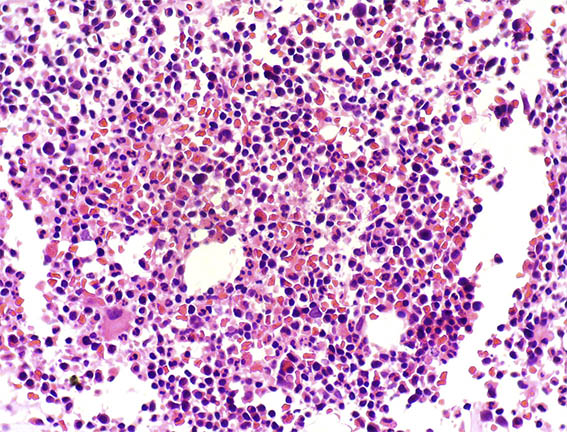

It is very inusual to find in a renal biopsy of patients with plasma cell proliferations, combination of filtered light chains in tubules (in this case causing cast nephropathy) and simultaneously deposition of paraproteins in tissues. This event is reported in approximately 2-5% of patients with renal disease due to plasma cell dyscrasias. The bone marrow biopsy demonstrated lambda positive multiple myeloma (Figures 13 and 14).

Figure 13. Bone marrow biopsy. H&E, X400.